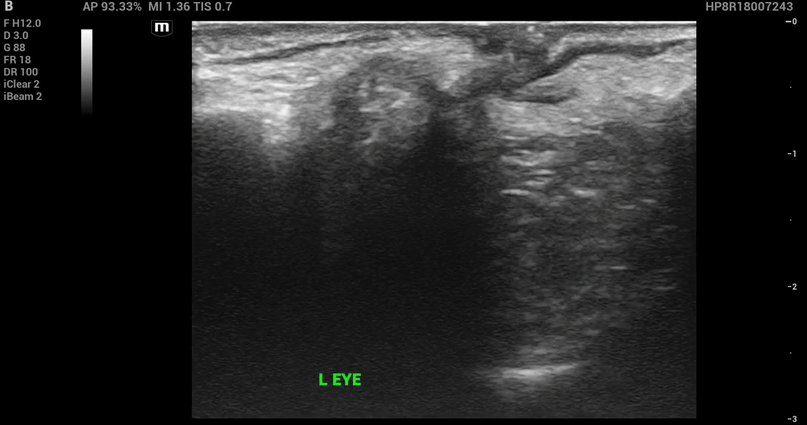

The bedside ultrasound:

Papilledema

Definition: Optic disc swelling due to increased ICP